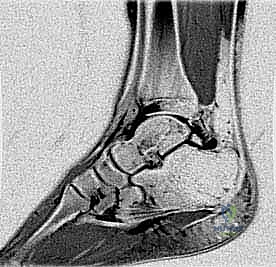

- التصوير بالرنين المغناطيسي (MRI): وهو الفحص الذهبي الذي يعتمد عليه الدكتور هطيف لرؤية الأنسجة الرخوة، وتحديد مدى الالتهاب، وتورم العظام، وحالة الأوتار المحيطة، وتأكيد وجود الانحشار بدقة متناهية.

لا يقتصر الانحشار على العظام فقط. في كثير من الحالات، يكون السبب هو تضخم أو التهاب في الأنسجة الرخوة، مثل الكبسولة المفصلية، أو الأربطة الخلفية (مثل الرباط الظنبوبي الشظوي الخلفي)، أو غمد وتر العضلة المثنية الطويلة لإصبع القدم الكبير (FHL). عندما تتضخم هذه الأنسجة، فإنها تُسحق بين العظام أثناء الحركة، مما يولد ألماً حاداً ومزمناً.

في بعض الأحيان، يولد الإنسان بعظمة إضافية صغيرة جداً في مؤخرة الكاحل تُسمى "العظمة المثلثية" (Os Trigonum). في الحالات الطبيعية، لا تسبب هذه العظمة أي مشاكل. ولكن عند الرياضيين أو الأشخاص الذين يمارسون حركات تتطلب ثني القدم للأسفل بقوة، تنحشر هذه العظمة بين عظمة العقب (الكعب) وعظمة الساق، مما يسبب التهاباً شديداً.

في حالات أخرى، قد يكون هناك بروز عظمي طبيعي في عظمة الكاحل يُعرف باسم "بروز ستيدا" (Stieda Process). إذا كان هذا البروز أطول من المعتاد، فإنه يتعرض للكسر الدقيق أو الاحتكاك المستمر، مما يؤدي إلى نفس أعراض الانحشار.